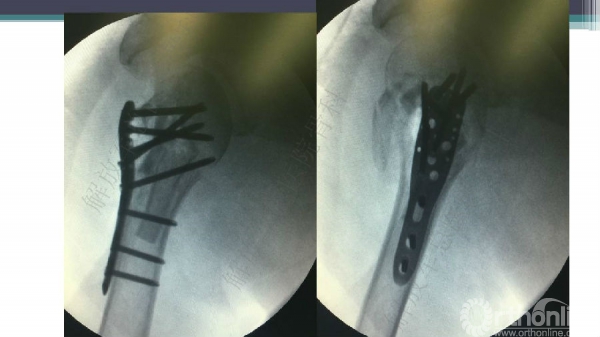

导 语:肱骨近端骨折仍是最常见的骨科损伤之一,尤其好发于老年人群。移位型肱骨近端骨折通常需要手术治疗,但是由于骨折粉碎、骨质较差,手术治疗往往会比较困难。随着锁定钢板的发明,使得并发症显著降低。但仍存在一些问题,对于内侧皮质不连续缺乏内侧可靠支撑,合并老年骨质疏松的病人,锁定钢板吊臂样结构就无法满足力学要求,随着康复锻炼可能出现断板、断钉、螺钉切出肱骨头等并发症。本期解放军总医院骨科专家们对老年肱骨近端骨折的问题与创新手术技术进行了详细讲解。